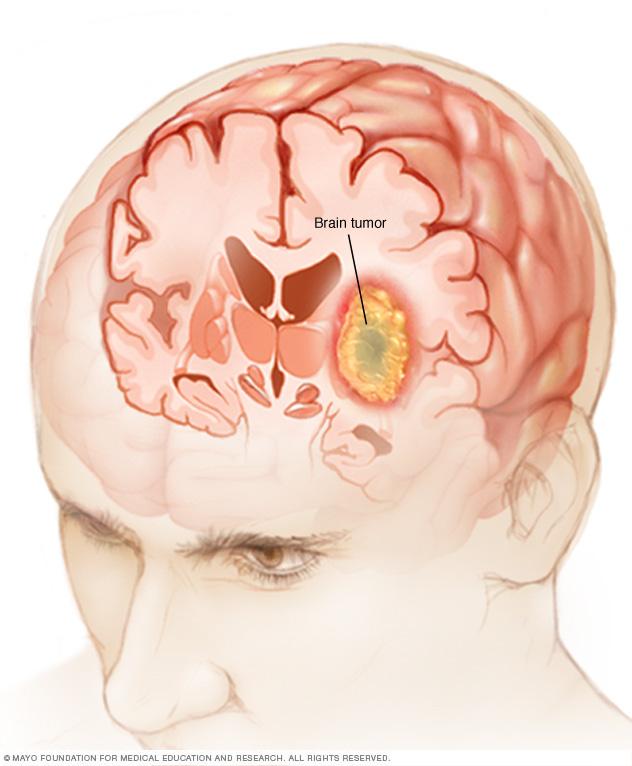

A brain tumor can form in the brain cells (as shown), or it can begin elsewhere and spread to the brain. As the tumor grows, it creates pressure on and changes the function of surrounding brain tissue, which causes signs and symptoms such as headaches, nausea and balance problems.